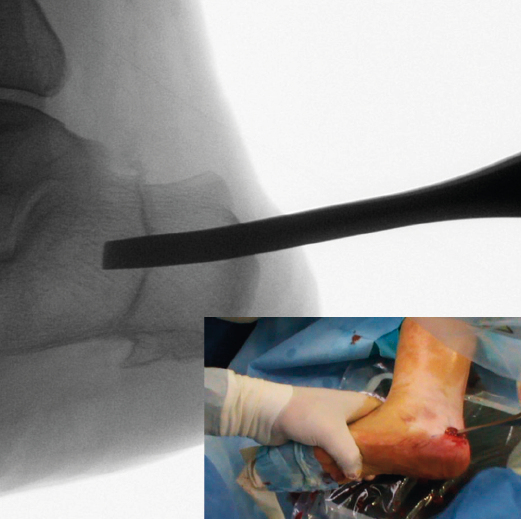

Figura 5. Imagen fluoroscópica del trazo dorsal de la osteotomía y su correspondencia en cirugía.

La fresa se coloca en línea con el trazo de osteotomía dibujado en la piel, primero el dorsal y después el plantar (Figuras 5 y 6), y va cortando la pared lateral y el hueso esponjoso del calcáneo y progresando paulatinamente hasta alcanzar la segunda cortical y cortarla cuidadosamente. Se recomienda no superar en 6.000 rpm la velocidad de la fresa para evitar la osteonecrosis térmica. A pesar de que el procedimiento se realiza sin isquemia para que la sangre refrigere el calor de la fresa, se recomienda que el ayudante aporte suero salino para contribuir a tal efecto.

Figura 6. Imagen fluoroscópica del trazo plantar de la osteotomía y su correspondencia en cirugía.